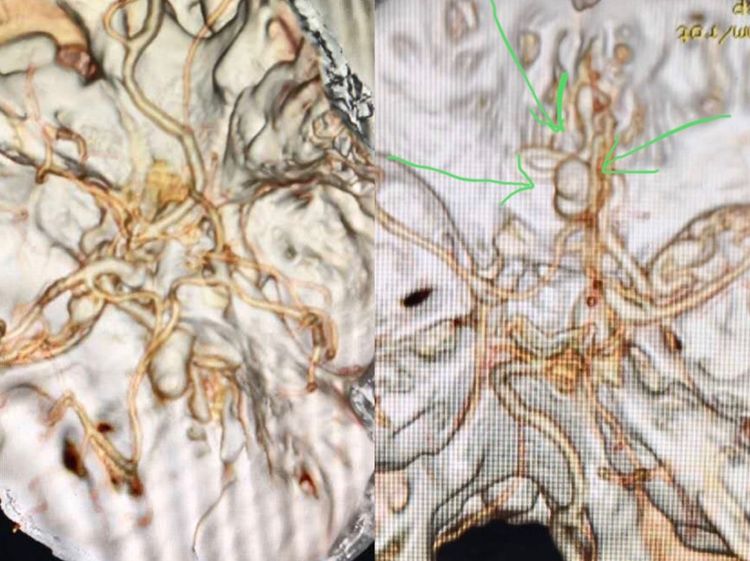

当完成双侧颈内动脉造影后我们发现,不是最初的诊断;

居然是一个前颅窝的硬脑膜动静脉瘘,供血来于双侧眼动脉的脑膜组。

我们认为的动脉瘤其实是引流静脉的球形扩张!

放完滤器、全身麻醉。首先要做一个全面的脑血管造影,特别是硬脑膜动静脉瘘的患者一定要做双侧颈内、外和椎动脉造影,必要时超选到造影。

这不,发现问题了:除了双侧眼动脉供血前颅窝的瘘以外,双侧颌内动脉分支也参与;而且居然又发现了一个后颅窝的瘘。这个后颅窝的瘘可以叫天幕区硬脑膜动静脉瘘吧!虽然没有出血,但可以看出来和前颅窝的瘘具有共同特点:皮层引流且引流不畅(静脉越来越多越来越细)。

这是一种危险结构,容易出血。所以,要干预!

我们首先经眼动脉注胶治愈了前颅窝的硬脑膜动静脉瘘,然后又经过脑膜动脉分支治愈了后颅窝的动静脉瘘。

图上标注的就是铸型的胶了。